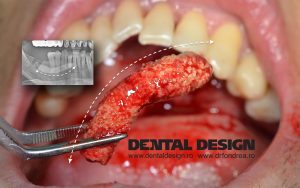

Cat ma costa doua implanturi? studiu de caz

In randurile ce urmeaza voi prezenta un caz. O sa incerc sa o fac intr-o...